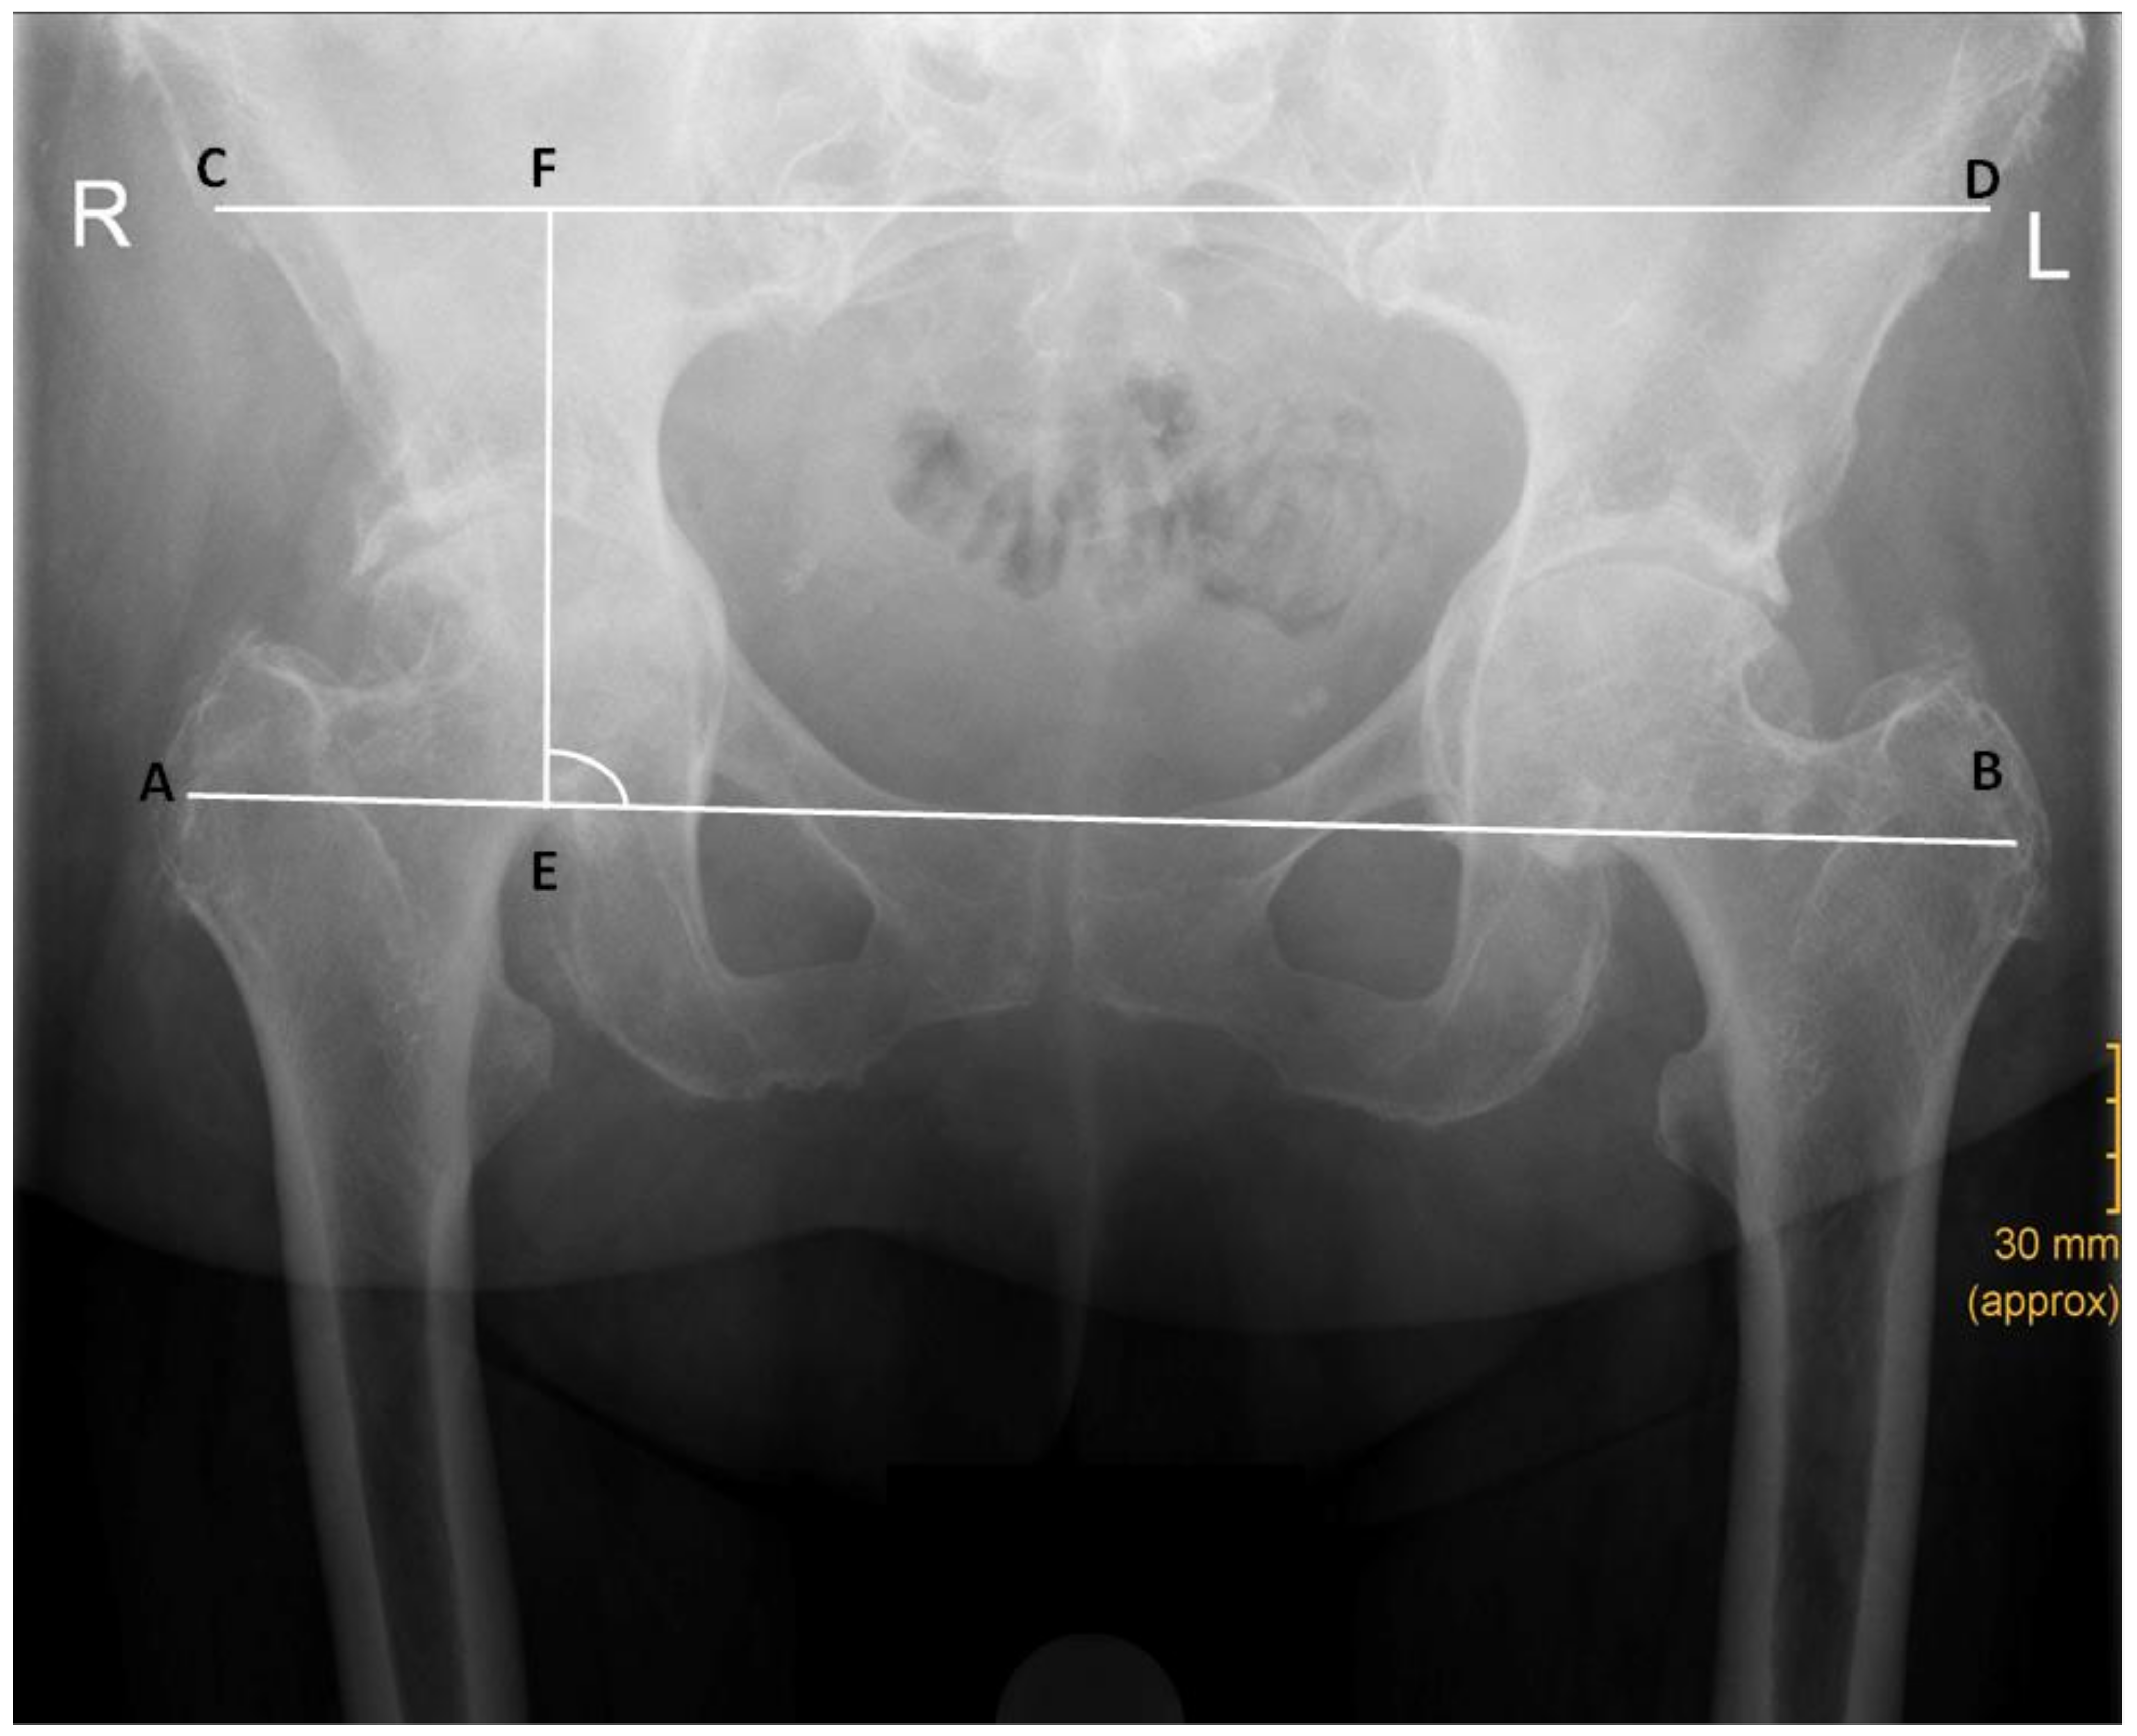

| LLD, preoperative (mean ± SD) | 4.49 mm ± 4.24 mm | 7.65 mm ± 6.76 mm | <0.00 |

| LLD, postoperative (mean ± SD) | 4.87 mm ± 4.12 mm | 5.41 mm ± 5.00 mm | 0.41 |

| AGVD (mean ± SD) | 108.59 mm ± 13.75 mm | 101.91 mm ± 14.36 mm | <0.00 |

| GT/ASIS (mean ± SD) | 1.19 ± 0.07 | 1.13 ± 0.07 | <0.00 |